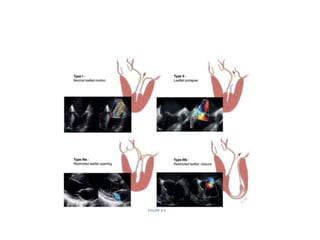

FUNCTIONAL CLASSIFICATION

• The triad includes etiology (cause of the disease), valve lesions (structural changes

resulting from the disease process), and leaflet dysfunction (alterations in leaflet